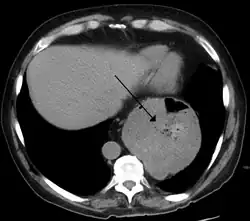

Hiátová hernie (jícnová kýla[1], hiátová kýla, latinsky hiatus hernia) je vyklenutí horní části žaludku trhlinou v bránici nebo jícnovým otvorem do hrudníku. Vážnější formy se řeší chirurgickým zákrokem.[2][3]